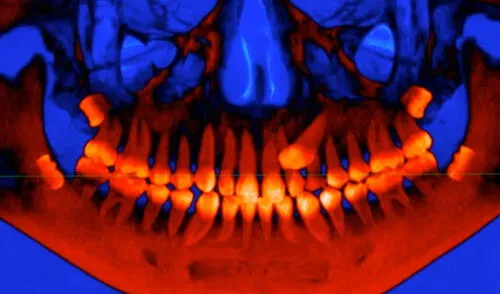

En un estudio publicado en la revista Science, Halszka Glowacka y Gary Schwarts, especialistas en antropología evolutiva de la Universidad de Arizona, en Estados Unidos, sugieren que el tiempo de desarrollo de estos molares están limitados principalmente por la frágil biomecánica de nuestro cráneo y músculos, más que por el espacio disponible para alojarlos.

Luego de modelar cráneos en 3D de 21 especies de primates, los investigadores descubrieron que la sincronización de nuestros molares adultos tiene relación con el delicado equilibrio de las articulaciones del cráneo en crecimiento.

Por tal motivo, para desarrollarse, los molares posteriores deben esperar la “seguridad” brindada por los músculos y huesos que los sostienen, tanto en fuerza como en sincronización.

Esto, además de asegurar las funciones básicas del sistema masticatorio, impediría que nuestra mandíbula se dañe por sí sola, una condición causada por nuestras cabezas más planas a comparación de nuestros ancestros simios.